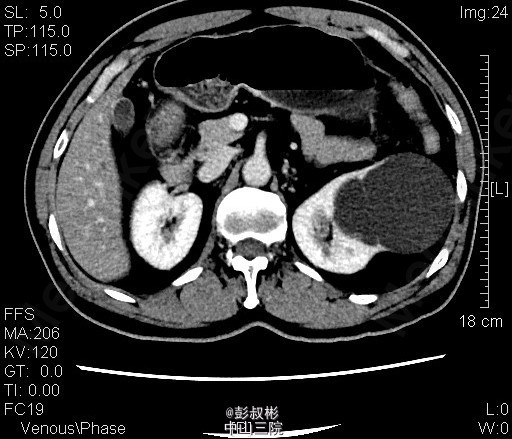

3、查体:腹稍膨隆,无压痛、反跳痛,未触及肿物,双肾区无红肿、隆起,无叩痛,双侧肋脊点、肋腰点无压痛。腹平软,双侧上中输尿管点无压痛,膀胱区无压痛。双侧腹股沟区未触及肿物。 4、CT:双肾多发囊肿,左肾囊肿较大,推压左侧肾盂肾盏。左肾小结石.轻度弥漫性脂肪肝

5、左肾囊肿 6、住院后完善相关检查,查血、尿常规,生化,凝血,心电图,胸片等未见明显异常。CT:双肾多发囊肿,左肾囊肿较大,推压左侧肾盂肾盏。左肾小结石.轻度弥漫性脂肪肝。经术前准备,行单孔腹腔镜下肾囊肿去顶术,手术顺利,术后予预防感染、营养支持等治疗,术后恢复较好,术后病理示:左肾囊肿。